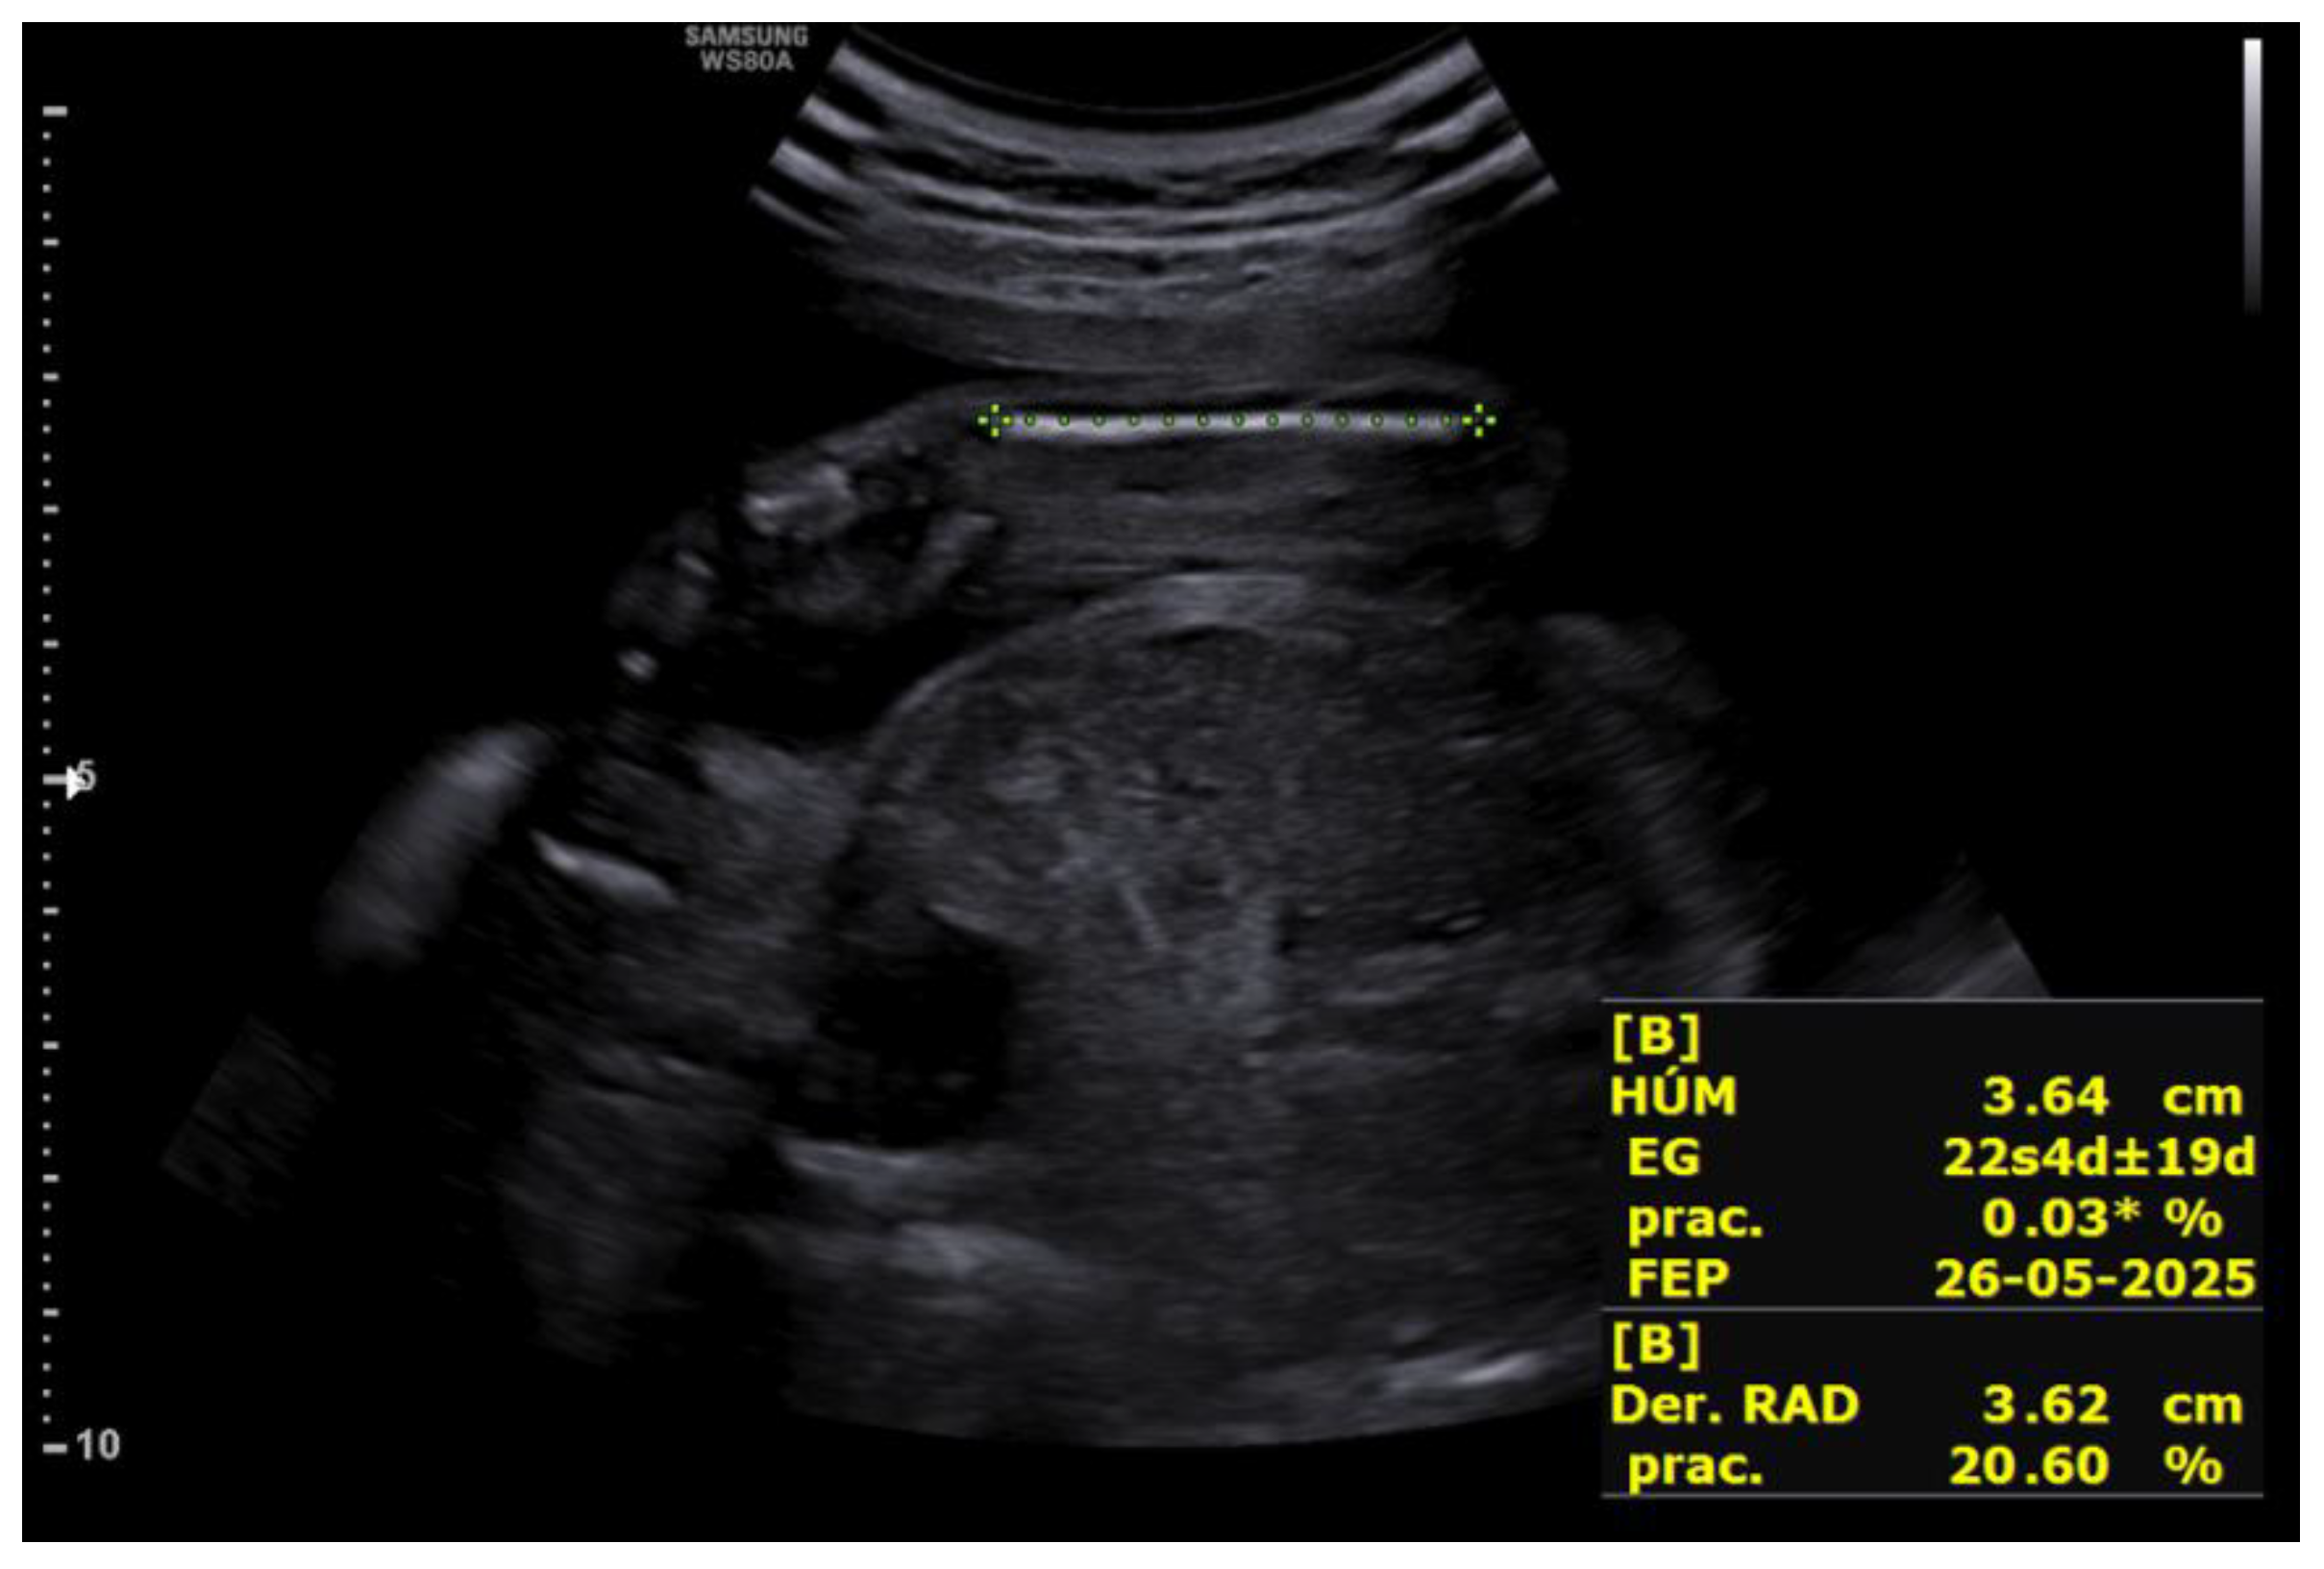

Upon receiving the genetic results for both fetuses, consistent with Peters-Plus syndrome, a consultation at 27+2 weeks was conducted to inform the parents about the genetic nature, clinical prognosis, and functional implications of the disorder, including possible ocular, neurological, skeletal, and systemic complications, as well as future reproductive options. A detailed neurosonographic assessment of both twins was also performed, revealing stage I intrauterine growth restriction in both fetuses associated with marked rhizomelia (Figure 4 and Figure 5).

Both fetuses demonstrated marked rhizomelia without additional evident skeletal anomalies. Intertwin estimated fetal weight discordance was 17.6%.

Figure 5. Rhizomelic shortening of the upper limb in the second fetus at 27+2 weeks.